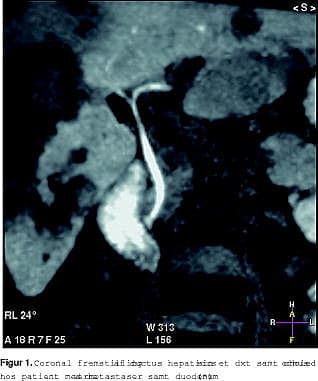

Ugeskrift for Læger havde den 13. juni 2005 et temanummer om galdesten. Det omhandlede også billeddiagnostik [1]. Til vor store forundring nævnes intet om en nyere MR-teknik. I dag laver man ikke kun MRCP (statisk billeddannelse ved hjælp af galdens vandindhold) men også funktionsbaseret fremstilling af galdevejene ved hjælp af enten kunstige stoffer eller paramagnetiske ernæringsstoffer (Figur 1 ).